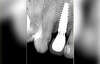

Cone Beam réalisé au cabinet pour déterminer la cause. On aperçoit une fracture vestibulaire, qui condamne la dent. Absence d’atteinte osseuse et le volume osseux autour de la dent est excellent.

Pose de la couronne définitive et radio de contrôle